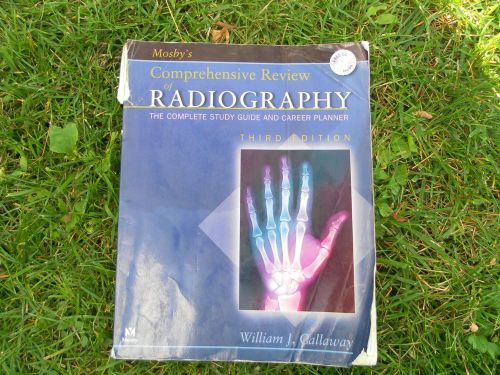

MOSBY'S COMPREHENSIVE REVIEW OF RADIOGRAPHY